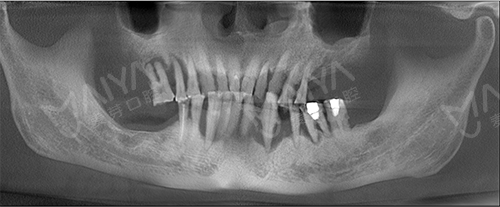

经过先进的CT拍摄发现,麦芽口腔院长指出,由于长期对口腔疏于护理,李老的牙周情况非常差,余牙松动,且牙槽骨萎缩、吸收,现存骨量无法进行传统的种植牙术式。

老李种植前全景片检查